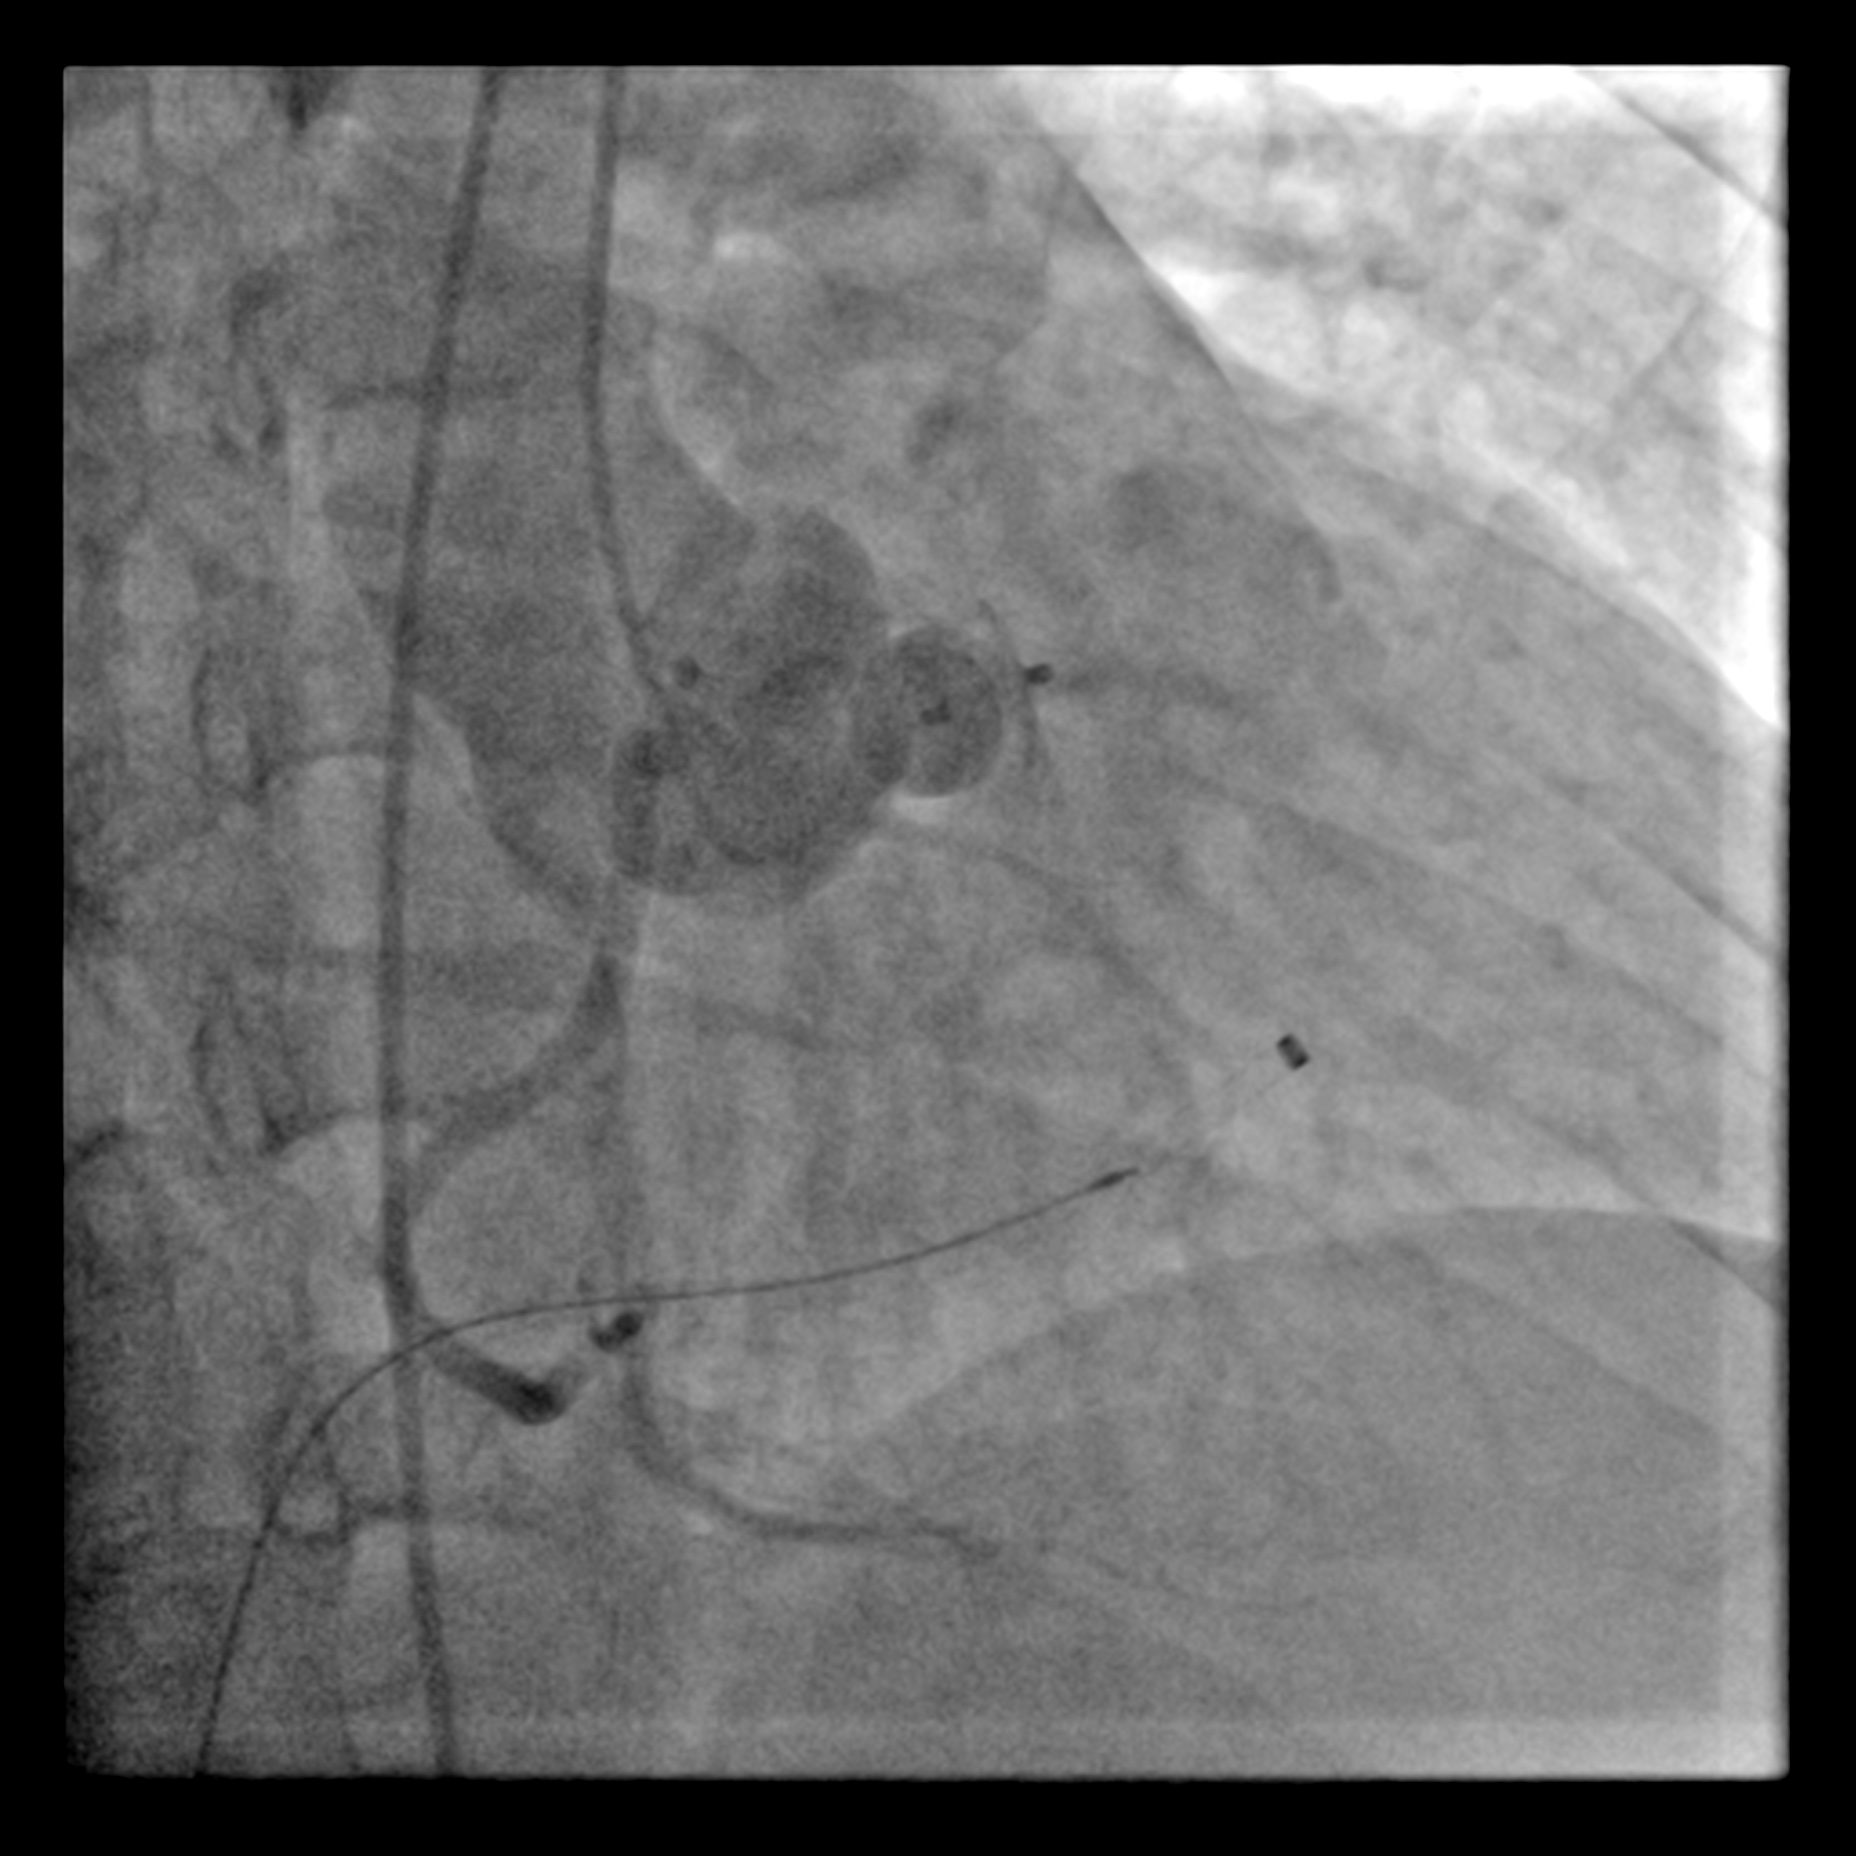

The procedure was commenced with one 7Fr sheath in right femoral vein & one 6Fr sheath in right femoral artery. From arterial access, a diagnostic Judkins right (JR) catheter 6Fr was positioned in right SOV. The defect was crossed with J-tipped Glidewire & subsequently advanced into right pulmonary artery. A Multipurpose (MPA) catheter was introduced via right femoral access & advanced into right pulmonary artery where the Glidewire was snared & externalised through the venous access. This created an arteriovenous wire loop. The delivery sheath was advanced over this loop wire, through the venous access, crossing the SOV's defect & positioned in ascending aorta. A 10-8mm KONAR-MFO VSD occluder (Lifetech) was smoothly deployed antegradely but left unreleased. A repeated non-selective aortogram was made with Pigtail catheter in ascending aorta confirmed preserved right coronary flow was & absence of aortic regurgitation. A trans-thoracic echocardiography confirmed the stable position & good defect sealing. The aortic valve demonstrated normal mobility without evidence of aortic stenosis & regurgitation. The occluder was then released under fluoroscopic guidance.